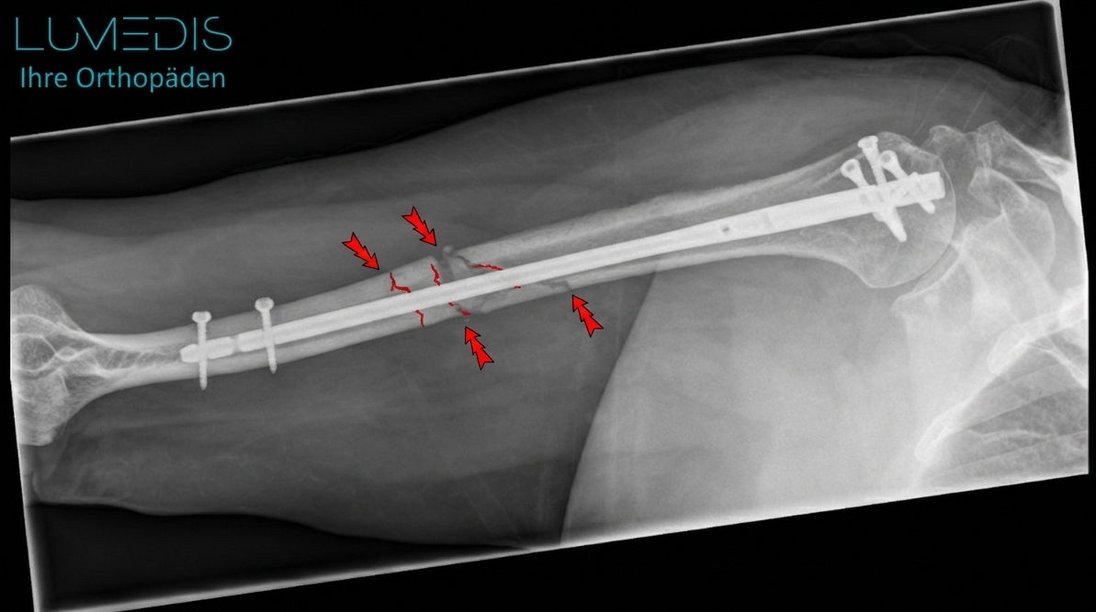

Röntgenbild eines Oberarmbruchs im Schaft vor und nach der OP mit einem Nagel

Röntgenbild eines Oberarmbruch vorher und nach Versorgung mit einem Oberarmnagel

Röntgenbild eines Oberarmbruchs links mit Platte und Schrauben

Bruch des Oberarms, der mit einem Nagel versorgt wurde